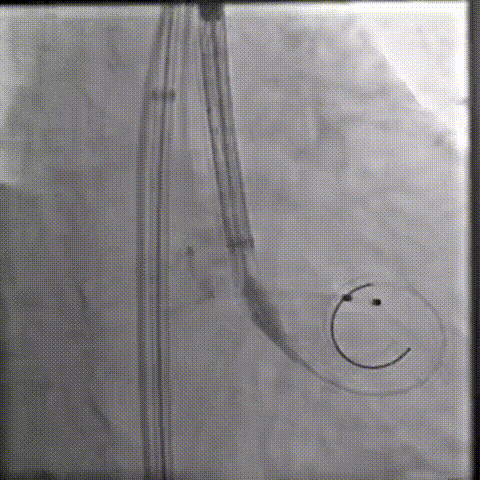

释放瓣膜

80%工作位评估

23球囊后扩